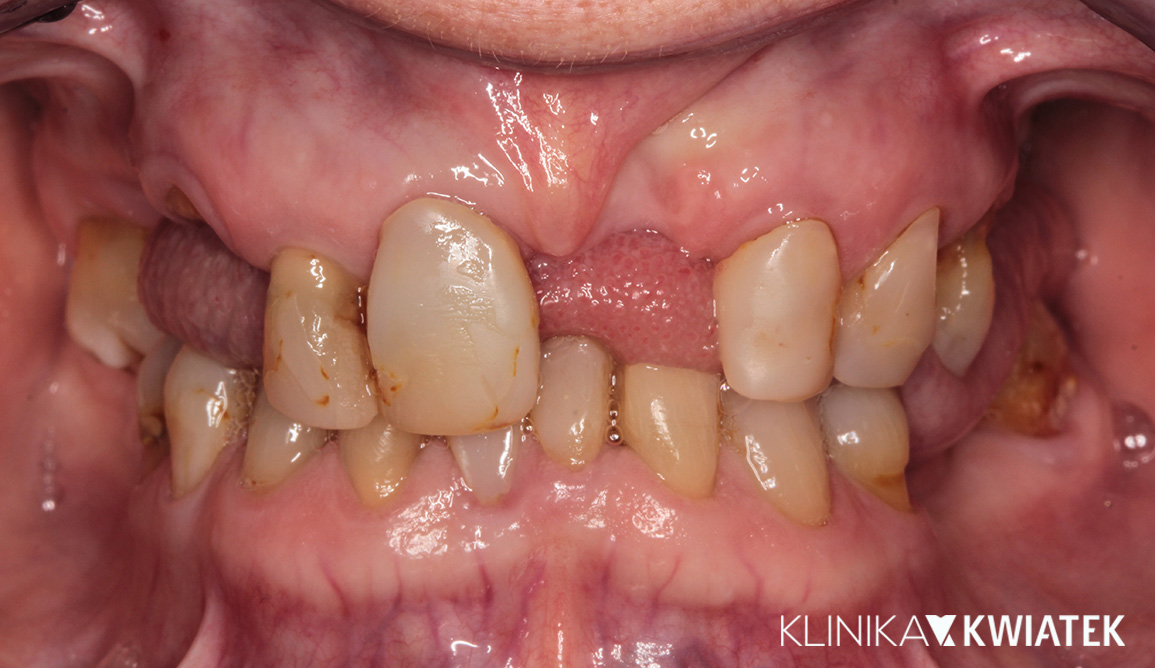

PRZED

PO

Odbudowy pełnołukowe na implantach w szczęce i żuchwie

Pan Krzysztof marzył o uśmiechu, który da mu pewność siebie i komfort życia – bez protez, bez kompromisów. Zakwalifikowano go do pełnołukowej odbudowy uśmiechu na implantach (All-on-6 / All-on-X), z natychmiastowym efektem estetycznym już tego samego dnia. Całość leczenia, od pierwszej wizyty po osadzenie ostatecznej pracy protetycznej, udało się zrealizować w zaledwie 4 miesiące. Efekt? Naturalny, trwały i piękny uśmiech, który wymaga teraz tylko jednej rzeczy – systematycznej higieny i kontroli, by cieszył przez długie lata.